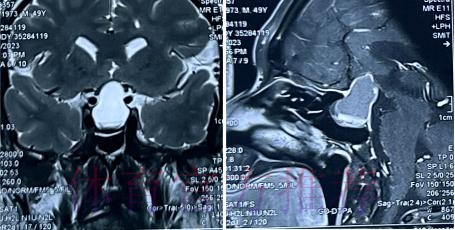

在高速对抗的现代足球里 现场肉眼和赛后情绪往往会放大对伤情的判断 一名球员倒地呻吟或无法坚持比赛 很容易被解读为韧带断裂 或肌肉严重撕裂 但真正决定恢复周期的关键因素 通常要到核磁共振检查之后才会明朗 因为核磁能在较早阶段清晰显示软组织 肌肉 韧带以及骨结构的微小损伤情况 对伤情做出更接近真相的分级判断 塞巴略斯此次就是典型案例 初步观感可能让人联想到更严重的伤病 但核磁提示伤情相对可控 没有出现完全断裂或大面积撕裂 也就意味着他不需要漫长的康复旅程 只要遵循医学建议 科学负荷管理 就有机会用较短的时间重新回到训练场和比赛中

塞巴略斯这一类型的技术中场 通常触球频繁 变向急促 需要大范围穿插跑动 在这种比赛习惯下 肌肉和韧带承受的累积负荷极高 尤其在密集赛程和高压对抗中 任何一次小小的失衡或强硬对抗 都可能放大为潜在伤病 因此外界对他伤情格外敏感 并非夸张反应 而是基于过往大量案例得出的经验判断 从厄德高 德布劳内 再到其他同类型中场 很多球员都在职业生涯某个阶段与伤病长期共存 一旦错过最佳治疗和恢复窗口 轻伤有可能拖成旧患 进而影响球员的爆发力 节奏控制能力乃至职业寿命 在这一背景下 经核磁共振检查确认 塞巴略斯伤情没有预期严重 其实反映的是球队在医疗体系 与负荷管理上的相对成熟 至少在第一时间 做到了科学评估 而不是情绪化处理

足球历史上 不乏因为伤情评估偏差而延误治疗的例子 某些球员在初诊时被认定为普通拉伤 结果因为没有进行完整的核磁共振检查 继续带伤出战 最终发展成严重撕裂 被迫长时间缺阵 从竞技层面来看 一次错误判断 可能直接改写一个赛季的走向 也可能在球员的职业生涯里留下不可逆转的隐患 与这些案例对照 塞巴略斯这次的过程显得更为规范 受伤后迅速接受医学影像检查 医疗团队根据结果评估伤情等级 给出清晰恢复计划 俱乐部层面则通过官方渠道适度释出消息 在 保护隐私与满足公众关切之间 取得平衡 对比之下 可以看出 现代职业俱乐部在伤病管理上的专业程度 已远超十几年前更多依赖经验和肉眼判断的时代 同时也提醒公众 不要被比赛画面中的瞬间表现完全左右 而是学会等待更权威的医学信息

经核磁共振检查确认 塞巴略斯伤情没有预期严重 这一结果从某种意义上是一种系统胜利 首先是医疗系统的胜利 医疗团队在第一时间介入 选择最合适的影像学手段 明确伤情边界 避免了盲目乐观或过度保守 其次是管理系统的胜利 俱乐部没有急于利用球员的意愿 扮演所谓硬汉形象 而是尊重科学节奏 为他预留足够的恢复空间 再次是沟通系统的胜利 球员 经纪人 医疗小组和教练组之间保持信息畅通 能够在保护球员未来和保证球队眼前成绩之间找到平衡点 正是这些系统共同作用 才让一次看似危机四伏的受伤 逐步转化为可控 可恢复的阶段性波折